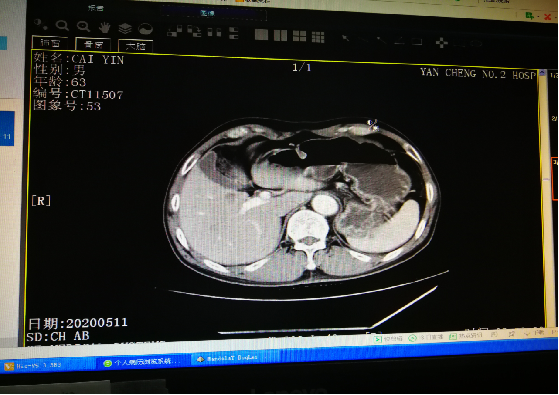

影像学检查: